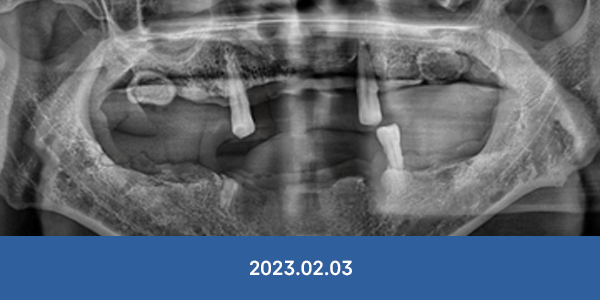

"대학병원 가보랬는데..."

서울감동치과는 가능합니다!

개원 7년간 대학병원 전원율 0% 달성

• 잇몸뼈가 완전히 없는 경우

• 전체 치아가 상실된 경우

• 치주가 심하게 녹은 경우

• 아래턱 신경과 바로 붙은 경우